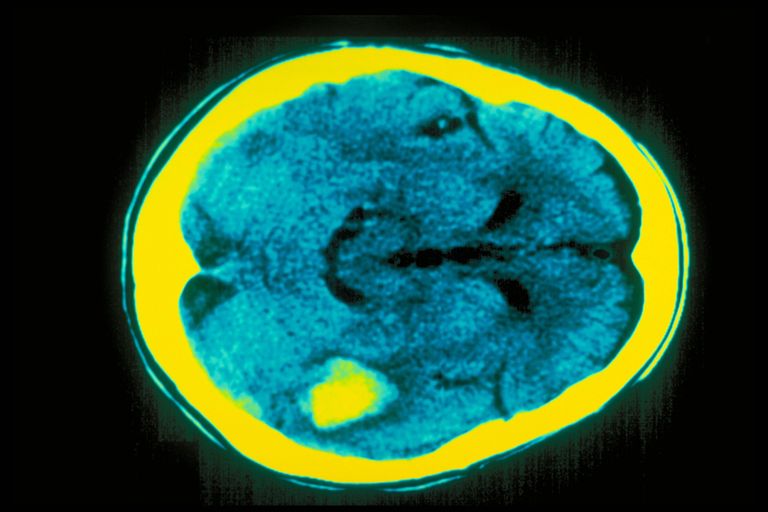

وبحثت المراجعة في الفروق بين الجنسين في معدل السكتة الدماغية الإقفارية والتي تحدث عند انسداد الأوعية الدموية، مما يؤدي إلى قطع العناصر الغذائية الأساسية والأكسجين عن الدماغ، وفي غضون دقائق، يمكن أن تبدأ خلايا المخ في الموت.